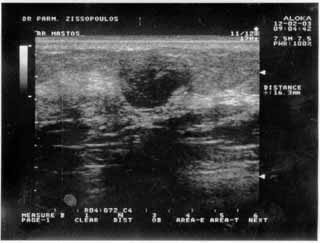

Για την καλλίτερη απόδοση της εξέτασης απαιτείται κεφαλή linear τουλάχιστον 7,5 ΜΗΖ. Ωστόσο και με κεφαλές 3,5 και 5 ΜΗΖ μπορεί κανείς να έχει καλά αποτελέσματα.

Oι τελευταίες 4 απεικονίσεις έγιναν με ειδικό για μαστό ηχοβολέα linear, εναλλασσομένης συχνότητος 7,5-10ΜΗΖ.